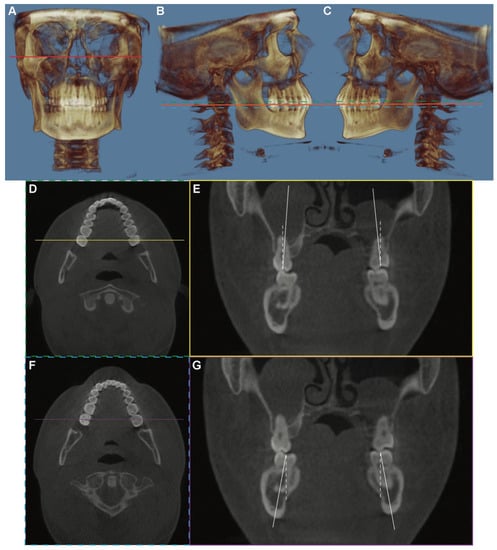

2.2. Imaging Analysis